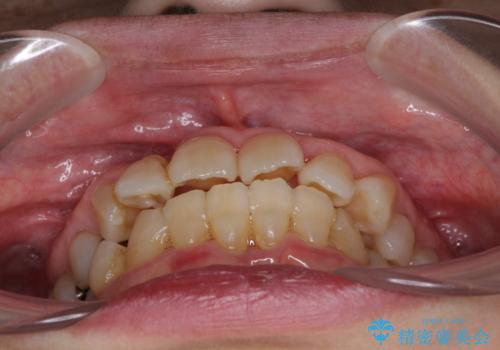

- 歯の欠損や歯肉からの出血などを気にして来院された患者様です。

診査の結果、歯周病であることが分かり、抜歯が必要な歯も見受けられました。

骨造成やインプラント、歯周外科、歯肉移植、矯正など、多くの処置を組み合わせて治療を行うこととしました。